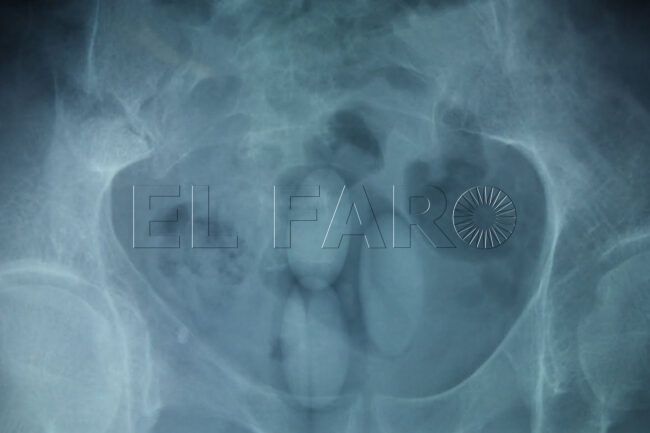

Uno de los pasajes más duros que relata en la entrevista tiene como escenario Ceuta y Jerez. Tras preparar a toda prisa varias bellotas de hachís para transportarlas, una de ellas quedó mal sellada y casi se abrió en su estómago. “Me tiré tres días en la cama doblado, con dolor de estómago. Aguantando por no ir al hospital porque si iba me cogían”, confiesa. La situación lo puso entre la espada y la pared: acudir a urgencias suponía exponerse a ser detenido, pero quedarse en casa significaba arriesgar la vida.

Durante horas notó los efectos del hachís en su organismo, boca pastosa, mareos y un dolor insoportable. “Ya me estaba notando colocao con el hachís. Me dije: Luis, ya la has liado”, recuerda en tercera persona. El desenlace, aunque no fue trágico, lo dejó marcado: el plástico se había abierto parcialmente dentro de su cuerpo, y el propio organismo fue expulsando restos hasta que, finalmente, sobrevivió. “Estuve a punto de ir al hospital porque me moría. Lo pasé muy mal”, resume.